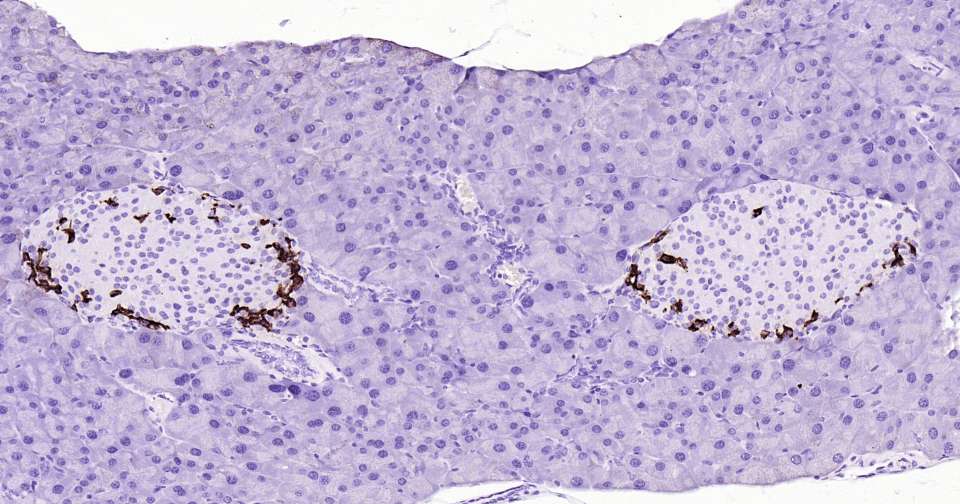

Immunohistochemical analysis of paraffin embedded mouse pancreas tissue slide using IHC0355M (Mouse Somatostatin 28 Kit).

Immunohistochemical analysis of paraffin embedded mouse liver tissue slide using IHC0355M (Mouse Somatostatin 28 Kit).